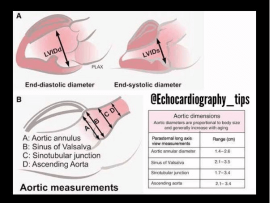

Lee masAbstract The guideline provides a practical step-by-step guide in order to facilitate high-quality echocardiographic studies of patients with aortic stenosis. In addition, it addresses commonly encountered yet challenging clinical scenarios..